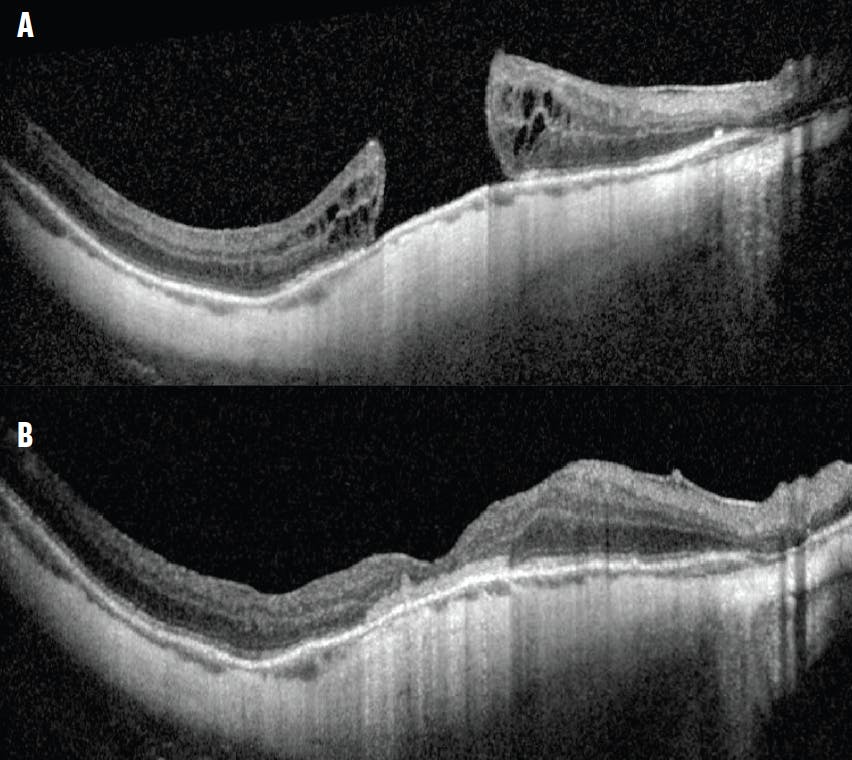

Case No. 2: A man in his 30s with high myopia (axial length approximately 30 mm) and a history of a giant retinal tear-associated RD experienced multiple recurrent RDs secondary to PVR and subsequent MH formation. The MH persisted despite a prior PPV with ERM and ILM peeling. The patient was referred to us for a second opinion and presented with a MH measuring approximately 1,250 µm at the narrowest inner aperture (Figure 2A). His preoperative VA was counting fingers.

He underwent PPV, peeling of residual vitreoschisis, ERM and ILM peeling, subretinal AM placement, and C3F8 gas tamponade (Figure 2B).

Figure 2. Preoperative OCT imaging shows a large MH measuring approximately 1,250 µm (A). Postoperative OCT imaging shows MH closure after PPV, peeling of the residual vitreoschisis, peeling of the ERM and ILM, subretinal AM placement, and C3F8 gas (B).

In contrast, the MH in the second case had an anvil configuration with slight elevation and cystic changes of the edges. In general, this configuration suggests that there may not be significant adhesions at the MH edges. In this case, an AM was easily inserted under the edges without the necessity of first lysing adhesions.